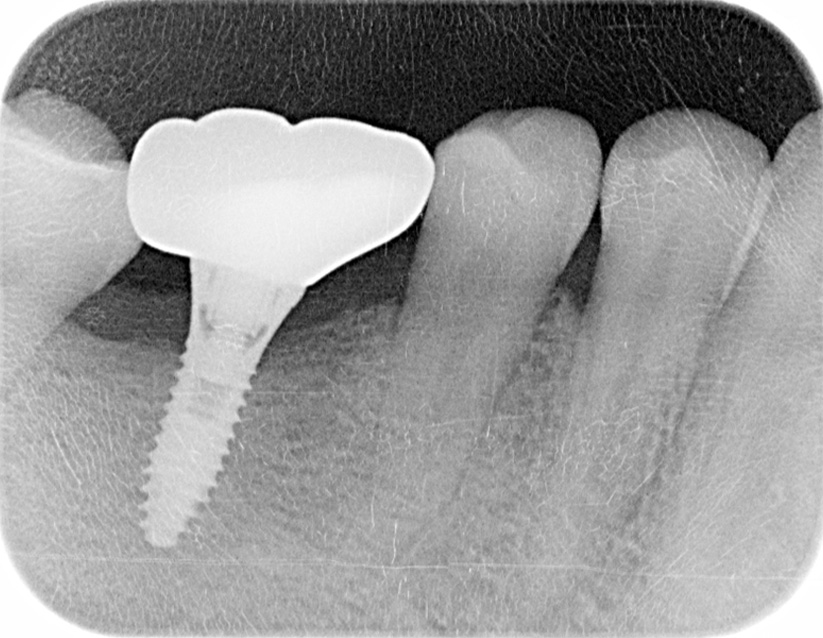

インプラント手術を行いました。

レントゲン画像 -

インプラント手術から3ヵ月後、型どりをして、仮歯を製作しました。

仮歯の調整期間を経て、セラミックの歯が入りました。

レントゲン画像 治療前 インプラント治療後